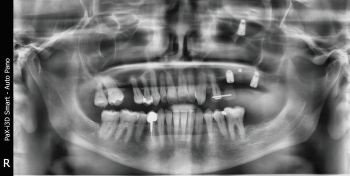

X-rays exams (i.e. OPG and CBCT) revealed the position of the displaced implant, which subsequently migrated near the ostiomeatal complex (OMC). It’s worth pointing out that immediately after their displacement, dental implants are usually located on the floor of the maxillary sinus or in the immediate vicinity; after a while, the displaced implants start to migrate against the gravitational force in the direction of the maxillary sinus ostium (as reported in the present clinical case) thanks to the strong mucociliary clearance by the sinus mucosa as well as nasal and intrasinus pressure changes. Notably, no reactive changes of the sinus membrane were observed (Figs. 1–5).

When Implants Go Rogue

Fig. 1: Pre-op panoramic X-ray